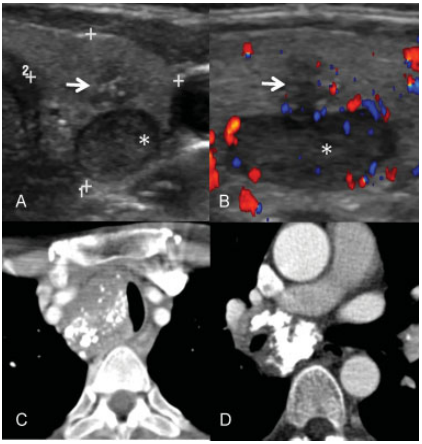

Carcinoma medular de tiroides en paciente con MEN tipo 2 con adenoma paratiroideo asociado (asterisco). La ecografía, corte axial (A) mostró una lesión hipoecoica, con márgenes mal delimitados y con microcalcificaciones (flecha), el corte longitudinal (B) con doppler color mostró una lesión sin flujo significativo (flecha). En la TC torácica con contraste intravenoso se objetivaron adenopatías a nivel paratraqueal alto (B) y paratraqueal bajo (C) con múltiples calcificaciones densas e irregulares características de la diseminación ganglionar en esa enfermedad.